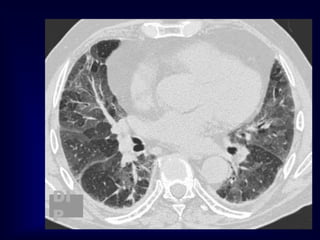

NSIP…

NSIP: initial reports of CT

spectrum of findings:

• Ground glass opacification with or

without areas of consolidation

• Linear opacities and reticular pattern,

but honeycombing limited or absent

• Lower zone predominance, may be

subpleural predilection

Park et al Radiology 1995;195:645

NSIP: initial reportsof CT spectrum of findings: • Ground glass opacification with or without areas of consolidation • Linear opacities and reticular pattern, but honeycombing limited or absent • Lower zone predominance, may be subpleural predilection Park et al Radiology 1995;195:645 Hartman et al Radiology 2000;217:701